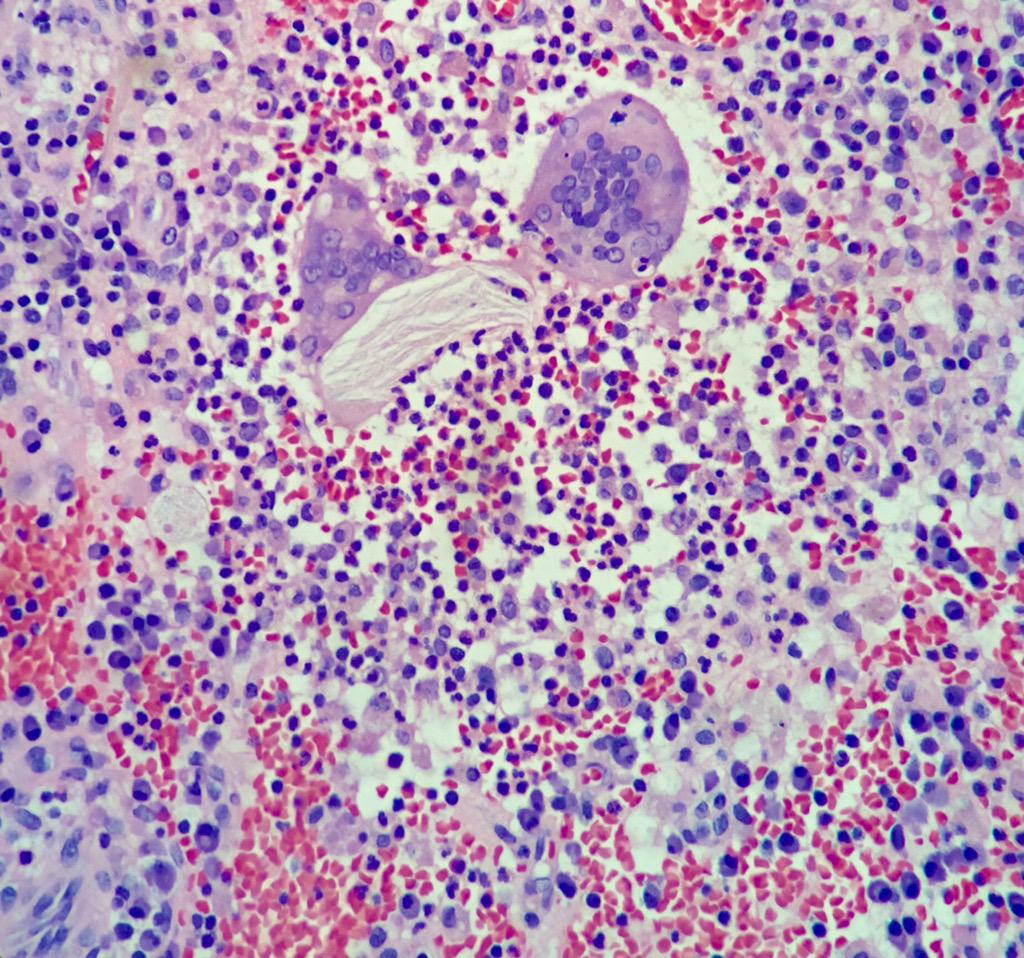

When a cosmetic surgeon offers dermal fillers on a regular scheme for a wrinkle, I really hope they have seen some some of these granulomatous reactions under a

#pathology#granulomatous#foreign#inflammation#giantcellhttps://twitter.com/Mvgs1706/status/1221922051692228608 …

Digesting multinucleated giant cells

#Dermatopathology#rupturedcyst#granulomatous reaction pic.twitter.com/arqWnwXBHo